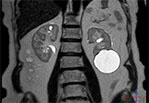

МРТ почек

Обе почки располагаются в типичном месте, обычной формы, контуры четкие и ровные, дифференциация коркового и мозгового вещества сохранена.

Почки обычных размеров: левая – 11,5х5см, правая – 12х6 см.

В паренхиме обеих почек определяются множественные кисты с однородным жидкостным содержимым размерами от 3мм до 11мм.

В нижнем сегменте левой почки визуализируется подкапсульная киста 55мм в диаметре.

Определяется не измененная, не расширенная чашечно-лоханочная система обеих почек. Оба мочеточника не расширены, прослеживаются фрагментарно.

Надпочечники обычно расположены, правильной формы, размеры и структура не изменены, дополнительных образований в их проекции не определяется.

Аорта и нижняя полая вена без особенностей, не расширены. Паранефальная клетчатка без особенностей. Лимфаденопатии на исследованном уровне не выявлено.

ЗАКЛЮЧЕНИЕ по снимку МРТ почек:

МР-картина простых кист почек.